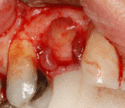

Soft tissue (gingiva) reconstruction

The gingiva surrounding a tooth has a 2–3 mm band of bright pink, very strong attached mucosa, then a darker, larger area of unattached mucosa that folds into the cheeks. When replacing a tooth with an implant, a band of strong, attached gingiva is needed to keep the implant healthy in the long-term. This is especially important with implants because the blood supply is more precarious in the gingiva surrounding an implant, and is theoretically more susceptible to injury because of a longer attachment to the implant than on a tooth (a longer biologic width).[28](pp629–633)

When an adequate band of attached tissue is absent, it can be recreated with a soft tissue graft. There are four methods that can be used to transplant soft tissue. A roll of tissue adjacent to an implant (referred to as a palatal roll) can be moved towards the lip (buccal), gingiva from the palate can be transplanted, deeper connective tissue from the palate can be tranplanted or, when a larger piece of tissue is needed, a finger of tissue based on a blood vessel in the palate (called a vascularized interpositional periosteal-connective tissue (VIP-CT) flap) can be repositioned to the area.[25](pp113–188)